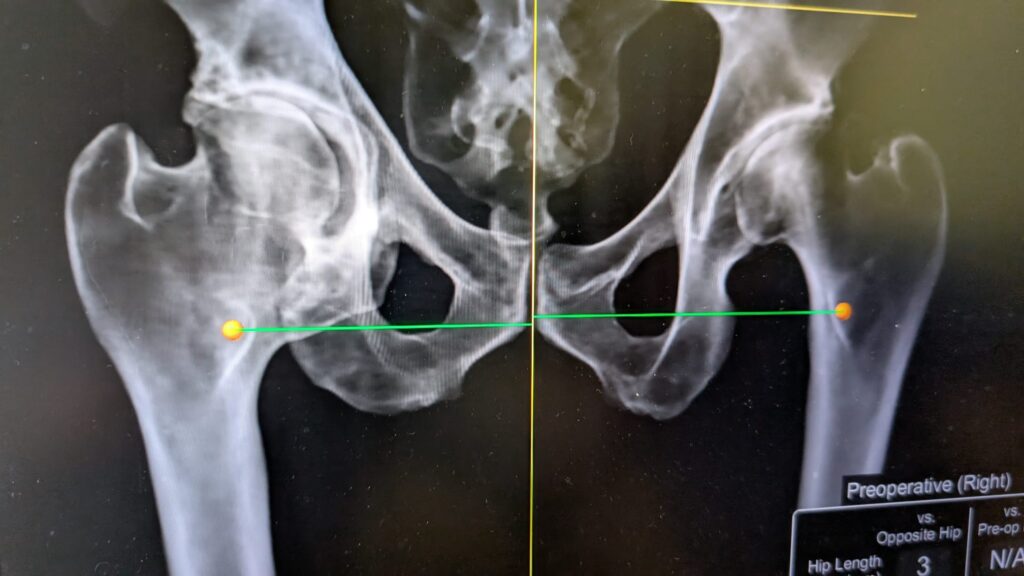

Planning, Luck, and the Revision Hip: When Plan A Needs a Plan F

Case Summary 76-year-old lady BMI 37 Right THR performed 19 years ago Comorbidities: Heart failure Hypercholesterolemia High BMI Presented with 3 dislocations in 3 months Dislocations occurred with trivial movements Patient had completely lost confidence in her right hip Planning, Luck, and the Revision Hip: When Plan A Needs a Plan F Planning, Luck, and…